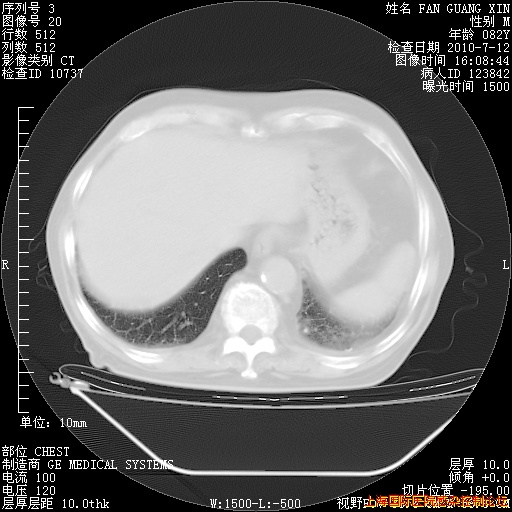

今天复查CT

回复

整整相隔30天的肺部CT好像有所好转啊。甲强龙减量第3天,需要观察体温。